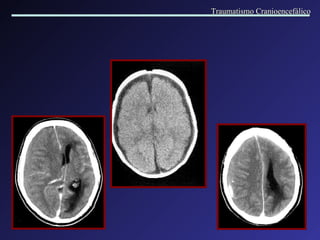

Formado entre o crânio e a dura, a partir do sangramento de vasos meníngeos. Associados a fraturas e outros tipos de lesões. Localização: Temporo-parietal. Quando > 40 ml = 100% mortalidade. Velocidade de instalação; efeito de massa. Intervalo lúcido. Hemorragia Extra axial   Hematoma Epidural Traumatismo Cranioencefálico

Hematoma Epidural  parietal direito : not a -se o aspecto lenticular da lesão e desvio da linha mediana. Traumatismo Cranioencefálico

Hemorragia Extra axial Hematoma Subdural Agudo   Formados entre a duramater e a aracnóide, por lesão de veias córtico-meníngeas. Este espaço é facilmente dilatável, possibilitando grandes acúmulos de sangue. Causas: quedas ou agressão. Lesões associadas. Intervalo lúcido. Coleção em crescente, com efeito de massa variável. A cirurgia normalmente está indicada. Traumatismo Cranioencefálico

Hematoma Subdural   Agudo Traumatismo Cranioencefálico